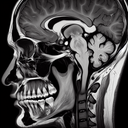

МРТ скронево-нижньощелепного суглоба

МРТ скронево-нижньощелепного суглоба – це неінвазивний метод діагностики, який забезпечує високоточне зображення м'яких тканин і суглобів. ### Переваги МРТ: - **Чітке зображення**: Дозволяє детально оцінити структурні зміни та аномалії. - **Безпека**: Процедура не використовує іонізуюче випромінювання...